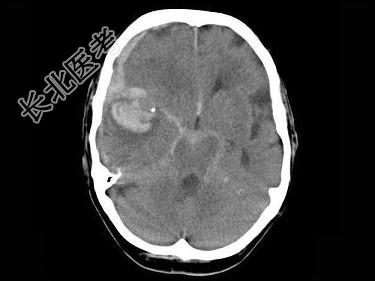

- 单项选择题女,79岁, 步行时突然摔倒,结合图像, 最可能的诊断是 ( )

A、右大脑中动脉破裂出血

B、脑转移瘤出血

C、脑膜炎

D、脑梗死

E、脑脓肿